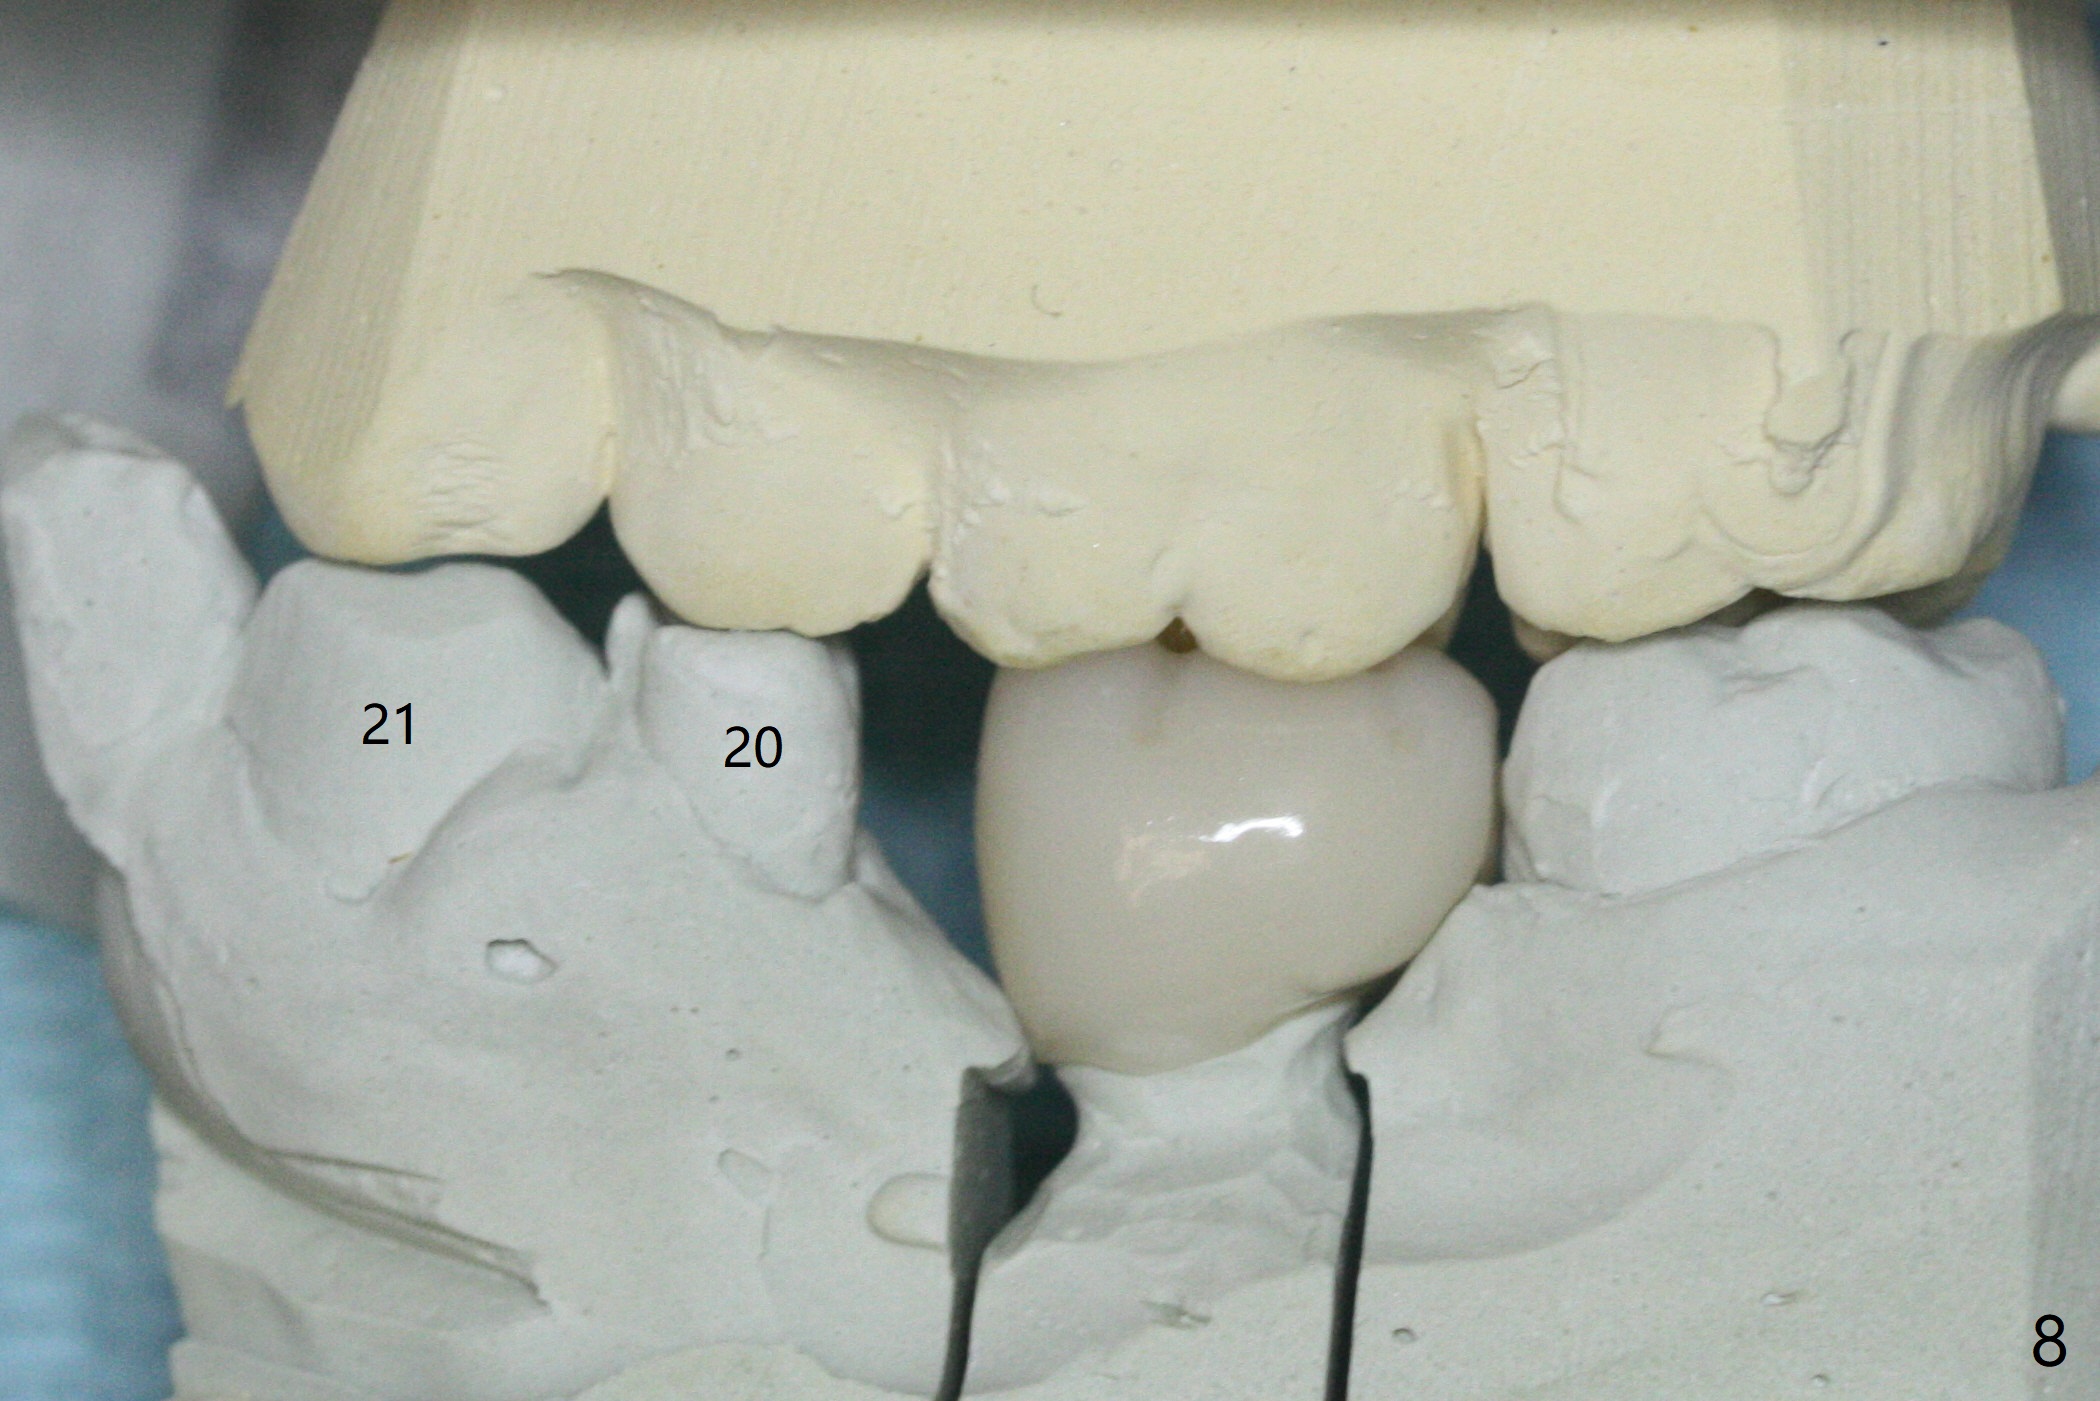

With 34 mg of Lidocaine and 17 mcg of Epinephrine (local infiltration), a 4.5x8.5 mm implant is placed with guide. The insertion torque is ~50 Ncm. It is placed in precise depth and in a short period of time (tolerable to the operators and patient, easier than mini-implant placement, Fig.1). There is no postop pain or paresthesia. The mesidistal position is within treatment plan (Fig.2). Miniimplants are placed to intrude #14 14 days prior. The teeth #16,17 and 32 are extracted 3 months postop. Minimal bone resorption at the crest is noted nearly 4 months postop (Fig.3). Bands and brackets are placed #18 upright 4 months postop (Fig.4 (14 niti wire)). The buccal and lingual view of the preop model shows that the supraerupted 1st molar (#14) has close relationship with the distal surface of the tooth #20 (Fig.5,6), accounting for the severe wear of the latter (Fig.8-11). The implant not only acts as an anchor to upright #18 in 4.5 months post banding (Fig.7 *), but also as an occlusal stop so that #18 has no interference to be moved. The stress on the implant results in radiating trabecular pattern (Fig.7,11 (9,11 months postop), as compared to before loading (Fig.1,3)). Restoring the distal contour of #20 with composite (Fig.12 C) makes it easy to close the space by adding porcelain the mesial surface of the implant crown. The crown/abutment is loose in China 7 months post cementation.